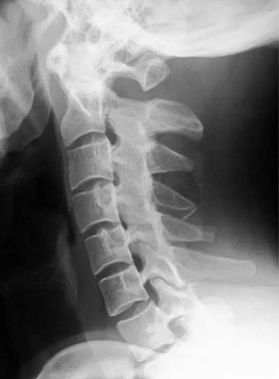

患者饺子今年14岁,平日特别喜欢通过手机、平板看电子书和玩游戏。今年因为新冠的影响,学校迟迟不能入校,所有课程通过网络视频授课,这就更加增加了手机、平板的使用时间。以往在学校时还有课外活动时间,回到家后孩子爸爸还会带着饺子打打羽毛球、篮球,今年这些却都不能做了,饺子在家只能网络上课、看电子书、玩游戏。有一天饺子告诉妈妈,脖子不舒服,还会感觉头晕,这一下妈妈着急了,带着饺子到医院看骨科,拍片子,显示颈椎曲度变直,大夫告诉饺子妈妈,回家养着吧,别总玩手机,不舒服了贴贴膏药,没事多活动活动。可回到家后小饺子还是总说脖子不舒服,头晕,这可怎么办呢?饺子的姥姥听说后,让饺子妈妈带着小饺子到我的门诊来,我和饺子的姥姥也算是老相识了,治了颈椎又治腰和膝盖。

来到门诊后,查体见:颈椎僵直,按压酸痛明显,压颈试验(-),臂丛神经牵拉试验(-)。给与了推拿正骨治疗,建议每周至少2次推拿,并且要结合功能锻炼,颈下垫浴巾卷辅助曲度恢复,因一周只出一次门诊,叮嘱饺子妈妈在我的学生门诊时找他治疗,周一找我治疗,就这样治疗了一个月后,症状消失了,拍片子,颈椎曲度也恢复了挺多。